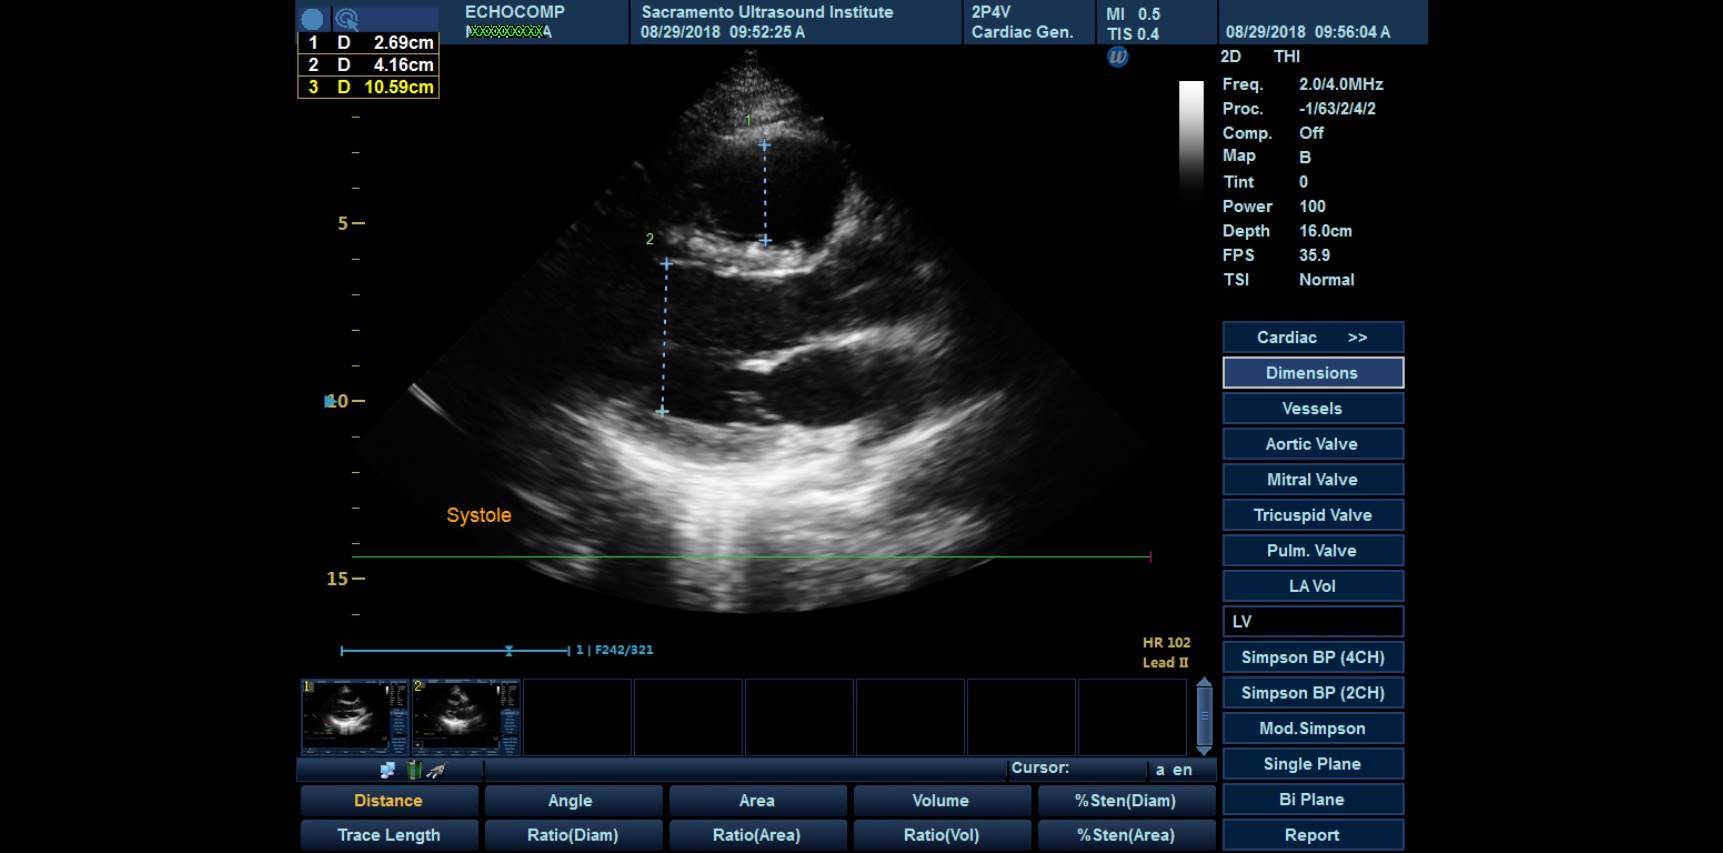

Sacramento Ultrasound Institute has announced the launch of, SonicDICOM PACS, its new Picture Archiving and Communication System (PACS) after partnering with JIUN Corporation, a software company headquartered in Fukuoka, Japan. The new PACS features a web-based DICOM Viewer and DICOM Server that is accessible online through SUI’s Student Portal. PACS is a system for digital storage, transmission, and retrieval of radiology images.

Digital Imaging and Communications in Medicine (DICOM) is the standard for the communication and management of medical imaging information and related data. DICOM is most commonly used for storing and transmitting medical images, enabling the integration of medical imaging devices such as scanners, servers, workstations, printers, network hardware, picture archiving and communication systems.

The system will enable students enrolled in the ultrasound and echocardiography programs to send the studies learned in class to be interpreted by instructors and radiologists; this will provide students a first-hand look at how their ultrasound studies translate into reports used for diagnoses of patients.